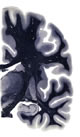

Hi-Resolution Sections · Cells (Nissl Staining) · Virtual Microscopy

Frontal sections (Nissl) from the Atlas Brain: Gallery Slice Single